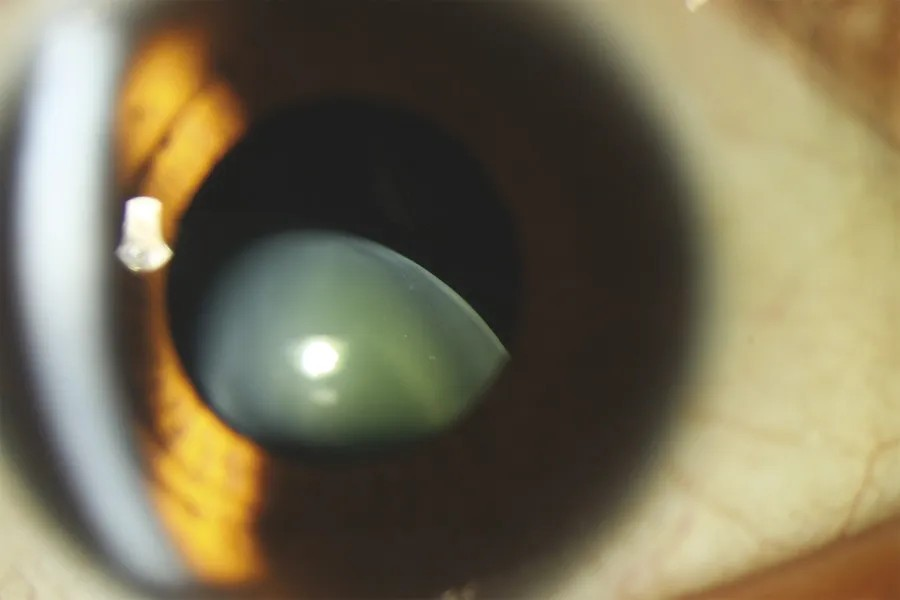

Hình ảnh: Mô phỏng vị trí TTT - Bình thường B. Lệch không hoàn toàn C. Lệch hoàn toàn vào buồng dịch kính

| TTT bị lệch (không hoàn toàn) | Phẫu thuật cố định IOL | Sau phẫu thuật |